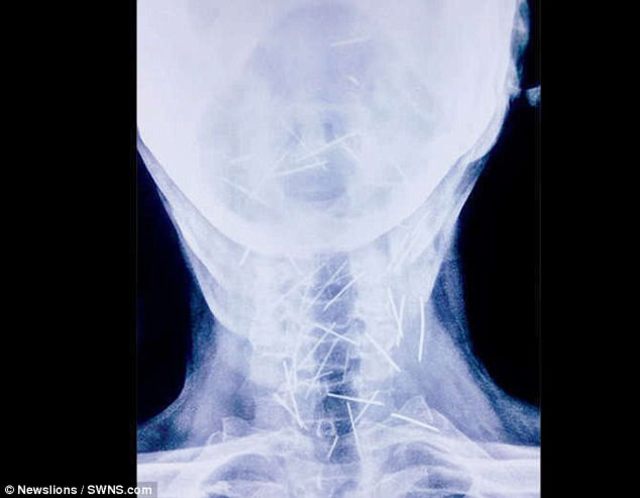

印度北方賈斯坦邦一名男子米納(Badrilal Meena),身上被檢查出有150根針,手、腳指頭經常感到疼痛,一開始先跑了1家醫院檢查出75根,再跑另一家醫院時再找到75根,他自己也不知道,為什麼身上會有這麼多根針,米納的兒子懷疑「是否遭到詛咒」?

根據《每日郵報》報導,現年56歲的米納是鐵路工人,身體多處尤其是首、腳指頭,經常感到疼痛,前往醫院檢查照了X光,發現喉嚨有40根針,腳上25根,2肢手臂上也各有1根,該家醫院不願意幫他動手術,最後跑了其他6家醫院,又檢查到身體裡,還有另外75根針,家人看到X光照片都非常傻眼,不禁質疑「家裡是否遭到詛咒」?

最後找到亞洲醫學科學研究所(AIMS)願意幫他動手術取出,主治醫師表示,這個手術相當危險,因為這些細小的針,分布在頸動脈、氣管等地,是一項很大的挑戰,目前手術都相當順利,已經取出了91根針,不過也耗盡米納的精神,其他地方是更難取出的部位,還要經過醫生討論,才能順利開刀取出。(翻攝每日郵報)